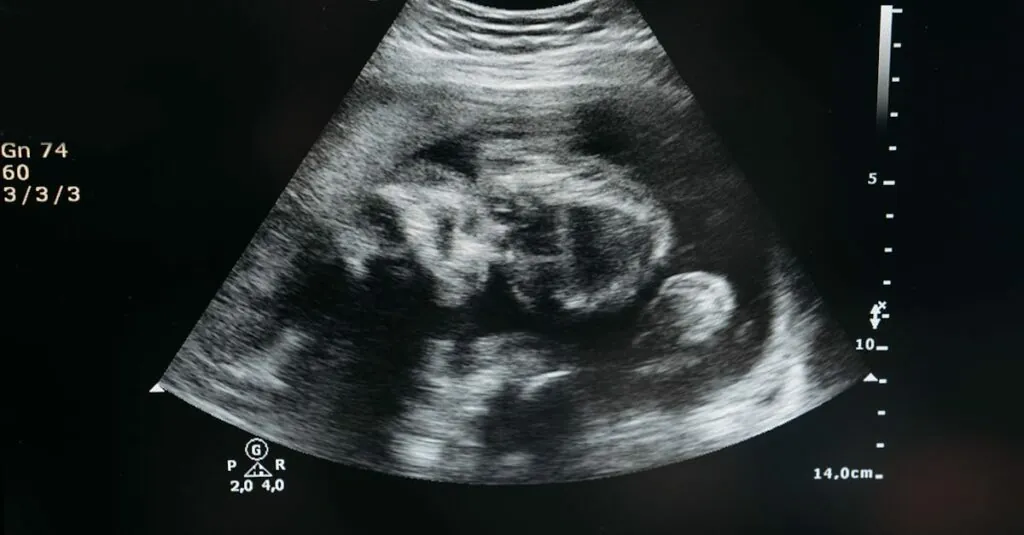

3D pregnancy ultrasound is an advanced imaging technique that provides expectant parents with three-dimensional visualizations of their unborn baby. This technology captures multiple images of the fetus from various angles, creating a multi-dimensional representation. Parents can observe their baby’s features in a way that traditional two-dimensional ultrasounds cannot achieve.

With 3D ultrasounds, clarity improves significantly, revealing details such as facial expressions and hand movements. High-resolution images enhance the emotional connection between parents and their baby, offering a more intimate experience. Expectant parents often appreciate the ability to see their baby smiling, yawning, or even waving.

Clarity in imaging improves with 3D technology. Parents see detailed features of their unborn baby, such as expressions and movements. This advanced visualization captures the fetus from different angles, revealing intricate details like fingers and facial contours. Medical professionals value this technology for accurately assessing fetal growth and spotting potential abnormalities. Expecting parents cherish these images, as they retain the clarity that traditional 2D images lack. Visualizing the baby in three dimensions fosters greater understanding of development over time.

This imaging technique employs ultrasound waves, which are sound waves that humans can’t hear. A transducer emits these waves, bouncing off the fetus and surrounding structures. The reflected waves return to the transducer, where software processes them into three-dimensional images. High-resolution imaging technology captures multiple angles, creating detailed visualizations that show features like the baby’s expressions and movements. These advancements in ultrasound technology allow medical professionals to assess fetal health more accurately while fostering a stronger connection between the parents and their baby.